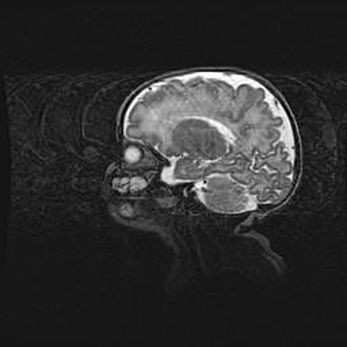

Мальформация Денди-Уокера. Киста задней черепной ямки.

Агенезия мозолистого тела.

Возраст: 2,5 месяца

Вес: 2420 г

Пол: женский

Окружность головы: 37 см

Срок гестации: 32 недели

Мальформация Денди—Уокера — редкий вид патологии ЦНС, представляющий собой врожденный порок развития каудального отдела ствола и червя мозжечка, ведущий к неполному раскрытию срединной (Мажанди) и латеральных (Лушка) апертур IV желудочка мозга. Для этогно синдрома характерна триада симптомов: гипотрофия червя мозжечка и/или полушарий мозжечка, кисты задней черепной ямки, гидроцефалия различной степени. В 70% случаев порок сочетается и с другими аномалиями головного мозга, в частности с агенезией мозолистого тела.